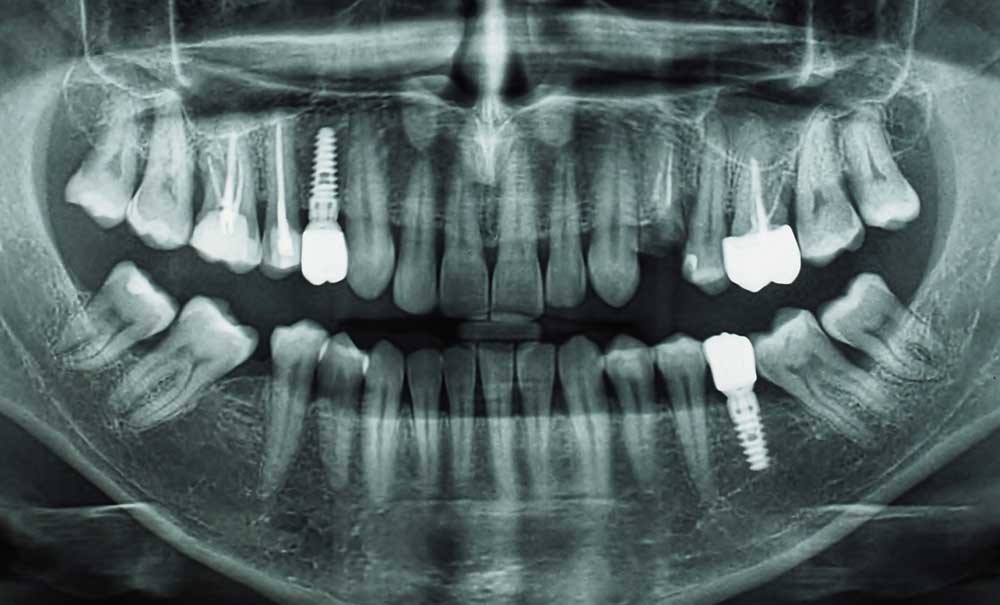

Les taux de succès en implantologie dentaire sont aujourd’hui très élevés, et les facteurs de risque de complications et d’échecs liés au contexte médical sont bien identifiés. Ainsi, on distingue aujourd’hui des facteurs de risque locaux, avec principalement les antécédents de parodontite [1] et l’irradiation cervico-faciale [2]. Les facteurs de risque généraux à considérer lors de l’interrogatoire médical comprennent l’immunodépression (secondaire à une pathologie ou à un traitement), le diabète non équilibré, les traitements anti-résorbeurs osseux (principalement ceux prescrits dans les cancers), mais également le tabagisme [3, 4]. Certaines situations sont des contre-indications absolues à l’implantologie dentaire (antécédents de radiothérapie au-delà de 40 Gy [5] et traitements anti-résorbeurs osseux dans le cadre des cancers), mais la plupart des risques locaux ou généraux sont aujourd’hui considérés comme des contre-indications relatives. Dans ce contexte, le tabagisme a certainement une place à part car il s’agit d’un facteur de risque modifiable.

Les effets délétères de la consommation de tabac ont été observés dans plusieurs études animales et sont caractérisés par une altération des paramètres péri-implantaires. Une diminution du contact os-implant et de la densité minérale osseuse a notamment été observée.